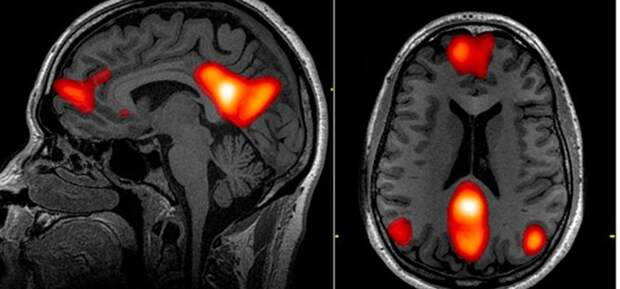

Среди множества серьезных симптомов COVID-19 странные неврологические эффекты, с которыми сталкиваются многие пациенты, считаются самыми неизученными. Внезапная потеря обоняния и вкуса была одним из первых необычных симптомов, о которых сообщили пациенты с COVID-19, но были задокументированы случаи инсульта, судорог и отека мозга (так называемый энцефалит).

Согласно отчетам и исследованиям, некоторые пациенты с диагнозом COVID-19 также […] The post Сканирование мозга показывает полный спектр аномалий COVID-19, которые не могут объяснить ученые first appeared on Информационное Агентство 365 дней.